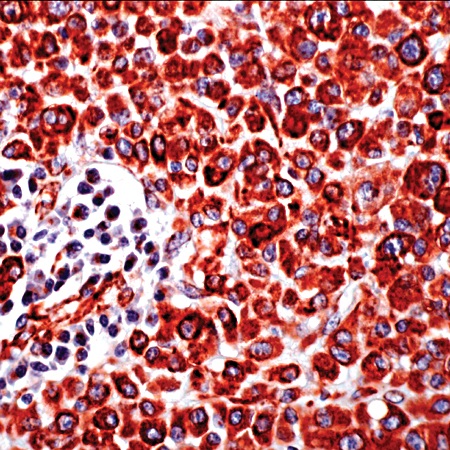

Vimentin (SP20)

Vimentin is the main intermediate filament protein in mesenchymal cells. This protein is believed to be involved with the intracellular transport of proteins between the nucleus and plasma membrane. Vimentin stains sarcomas of neural, muscle and fibroblast origin, but carcinomas which are generally negative. Melanomas, lymphomas and vascular tumors may all stain for Vimentin.